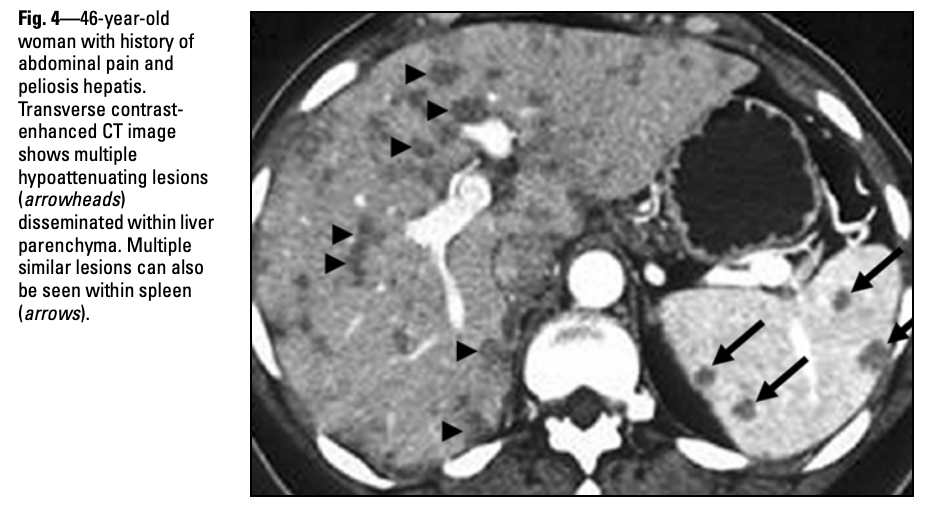

Dr Yuranga Weerakkody◉ et al.

Splenic peliosis is an unusual benign disorder characterised by the presence of irregular cystic blood-filled cavities.

Radiographic features

Ultrasound

May be seen as an echogenic mass lesion with numerous poorly defined foci of varying hypoechogenicity 5.

CT

On non-contrast-enhanced CT images, typically seen as a hypo-attenuating, multi-loculated lesion with well-defined septae within.

On contrast-enhanced CT images, the lesion may show significant enhancement with loss of definition of the lobules and septae. Fluid–fluid levels may also be present.